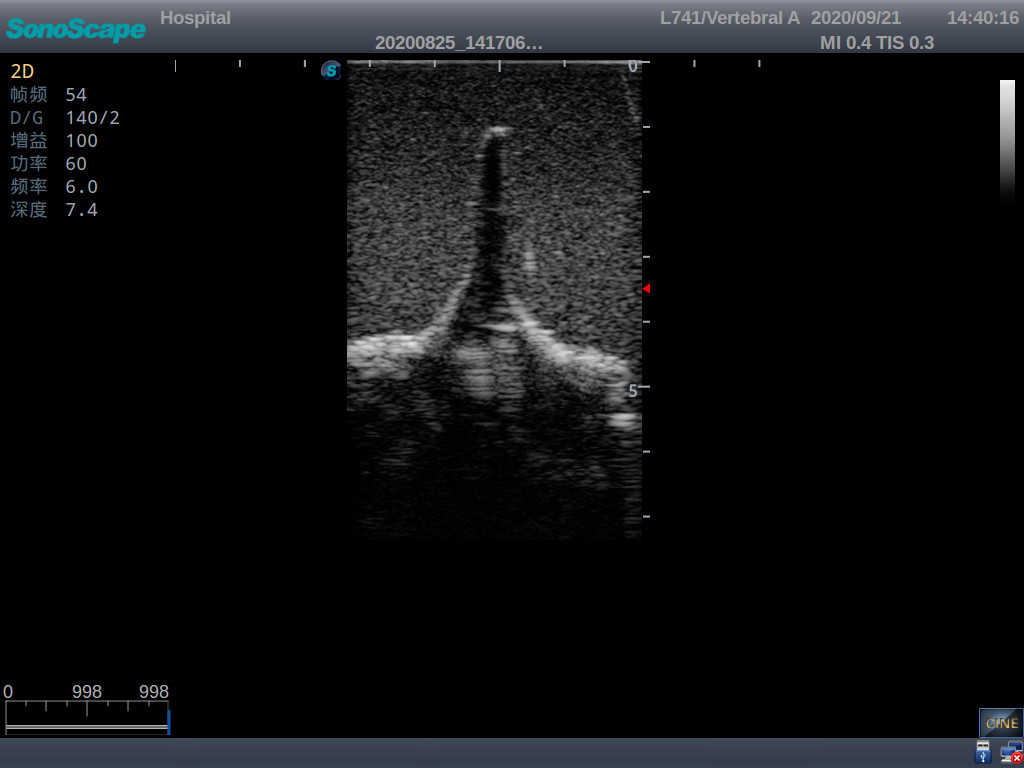

Model TYE1549.2

This model is an ideal choice for ultrasound-guided adult lumbar puncture training with true-to-life skin feel and touch, accurate anatomical structures as well as real clinical ultrasound images. Realistic resistance to needle tips and correct landmarks provide excellent hands-on experience.

2)  Real clinical ultrasound images